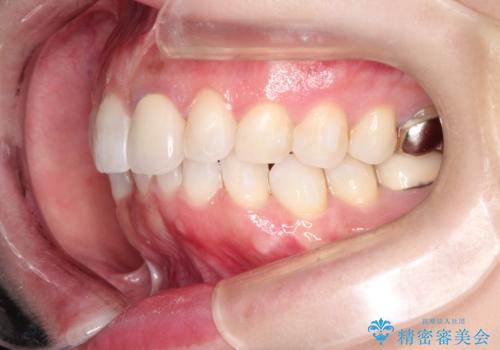

インビザラインによる非抜歯矯正 ガタガタな歯並びを整った歯並びへ

- 上下の全体的ながたつきが気になるとのことで来院されました。

マウスピースでの目立たない矯正を希望されたので、インビザラインでの治療となりました。

全体的に歯と歯の間にわずかに隙間を作り、歯を並べました。